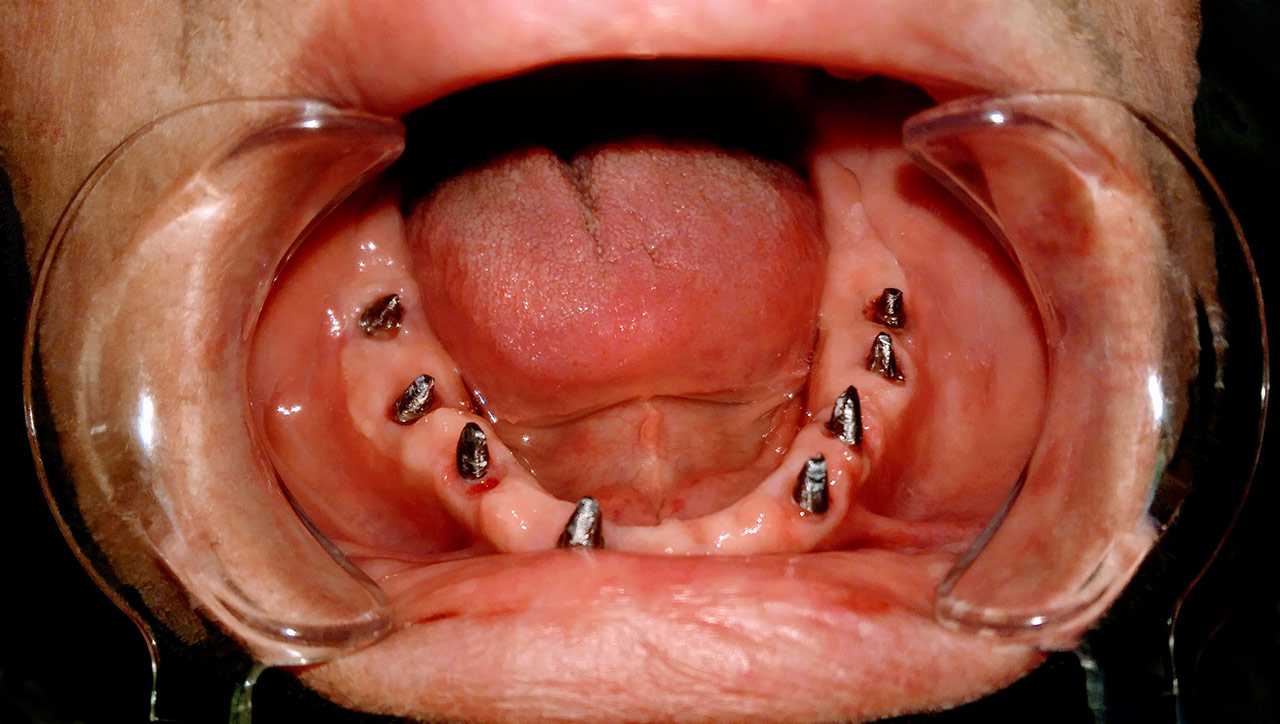

Elhanyagolt fogsor cseréje 2 nap alatt

2 nap alatt varázsoltuk ezt a szép esztétikus alsó, felső körhídat implantátumokkal megtámasztva a korábban elhanyagolt szájba. Az 1. nap 26 fogat távolítottunk el, mert annyira rossz állapotban voltak, és rögtön azonnal terhelhető IHDE svájci implantátumokat raktunk be, fentre 8, lentre 6 darabot. A sebeket összevarrtuk és intraorális szkennerrel digitális lenyomatot vettünk. 2 nap múlva pedig beragasztottuk a kész PMMA műanyag körhidakat. Dr. Kelemen Péter és a Symbion Fogtechnika munkája.